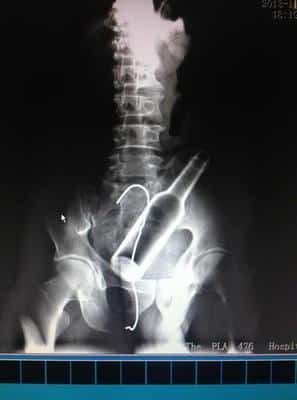

W końcu lekarze zdecydowali się na interwencję chirurgiczną, aby usunąć butelkę. Na szczęście, po zabiegu nastolatek był w stanie wrócić do zdrowia.